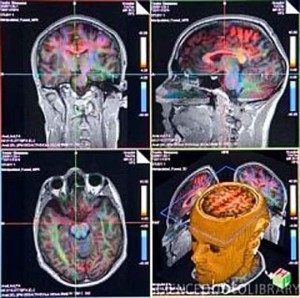

Sono stati identificati i circuiti cerebrali che presiedono alla sensazione, apparentemente ovvia, di trovarsi nel proprio corpo. A determinarla è...